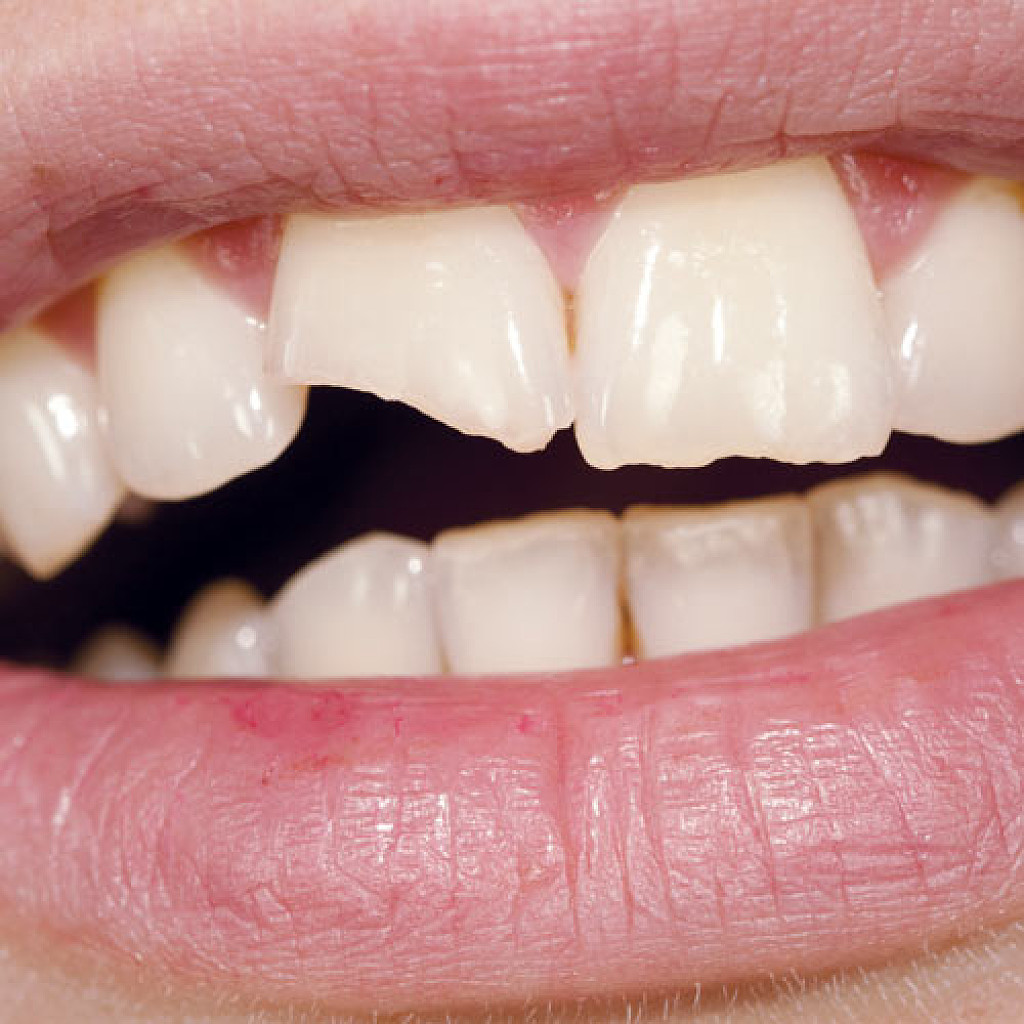

2. Fractured Cusp: Fractured cusps occur when a piece of a tooth’s chewing surface breaks off, typically near a filling. This type of fracture usually does affect your pulp or cause pain and typically can be repaired through a filling or crown.

According to a report in the Journal of Clinical & Diagnostic Research, fractured cusps are the most common type of longitudinal fracture. A number of conditions may cause them:

Teeth weakened by restorations

Large cavities

Age

Traumatic injuries

Abnormal biting habits, such as teeth grinding

If you do have a fractured cusp and experience pain or sensitivity to cold fluids, reach out to your dental professional for immediate attention.

3. Cracked Tooth: A cracked tooth is when a crack extends from the crown of the tooth toward the root, though the tooth is not split into pieces. This fracture is more extensive than a fractured cusp and, therefore, more likely to affect the nerve of the tooth. There are several possible causes for a cracked tooth, including:

Teeth grinding

Dental work that weakened the tooth

Trauma to the tooth

Treatment will vary based on the location and extent of the crack, which your dentist may need to investigate. If the nerve of the tooth is affected, an endodontist might perform a root canal treatment. If the crack extends down below the gumline, the tooth may need to be extracted.

4. Split Tooth: A split tooth is a complete fracture from the crown that extends below the gumline through the middle of the tooth. This is usually the result of an untreated cracked tooth, as the fracture extends over time, it can happen either suddenly or due to the long-term growth of the crack. The tooth may require extraction, but in some cases, an endodontist may save a portion of the tooth and complete a restoration to make the tooth functional.